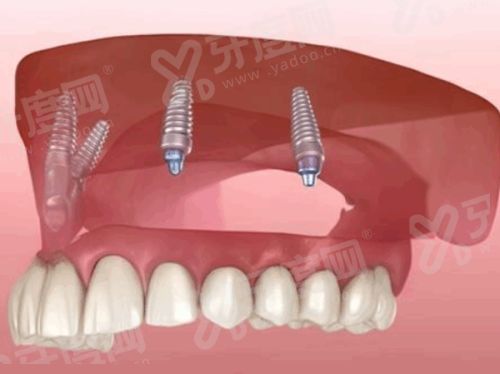

李凤元:主任医师。擅长口腔修复、种植牙、口腔外伤、口腔肿瘤等疾病。